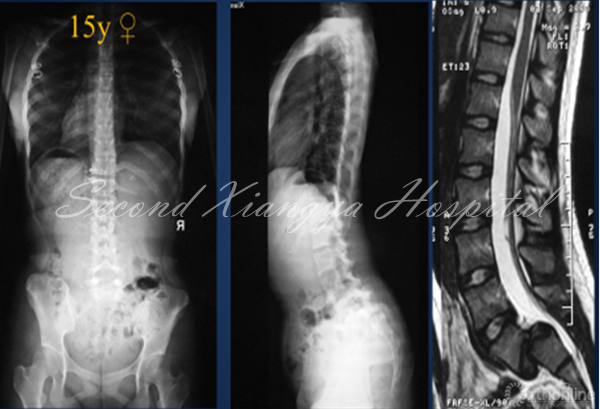

腰椎重度滑脱症定义是指椎体滑移率>50%,Meyerding>II度。青少年人群中发病率为2.4%,常累及L5/S1节段。发育,创伤,手术和病理是造成腰椎重度滑脱症的因素。依据SDSG分类,重度滑脱分为骨盆平衡,骨盆后倾和失平衡三种类型。从自然史讲,生长发育期间的腰椎重度滑脱症会出现进展,造成临床症状和脊柱矢状面失平衡,因而需要外科干预。

外科治疗腰椎重度滑脱症具有挑战性,如选择不当,往往会造成并发症,影响临床疗效和患儿日常生活。因此,笔者结合文献和自身经验,浅谈一下如何合理选择矫正方案以降低并发症。

• 青少年腰椎重度滑脱有进展风险

• 手术方式包括原位融合、部分复位或完全复位等

• 骶骨严重发育不良、腰椎前凸过大、矢状面失平衡,以及植骨方式不当是手术失败主要原因

• 具体手术方式应根据矢状面平衡状况和骶骨形态合理选择,以减少并发症发生.